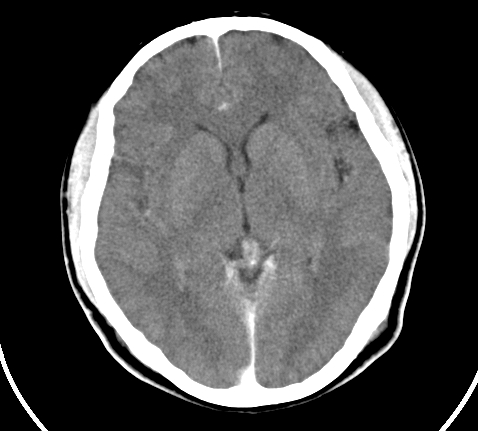

标题: CT23915:女 20岁 全身长疙瘩三年 今日多体位查 看看吧 [打印本页]

标题: CT23915:女 20岁 全身长疙瘩三年 今日多体位查 看看吧

神经纤维瘤病

支持神经纤维瘤。

支持 神经纤维瘤病。